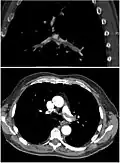

CT pulmonary angiography

CT pulmonary angiography (CTPA) is a pulmonary angiogram obtained using computed tomography (CT) with radiocontrast rather than right heart catheterization. Its advantages are that it is accurate, it is non-invasive, it is more often available, and it may identify other lung disorders in case there is no pulmonary embolism. The accuracy and non-invasive nature of CTPA also make it advantageous for people who are pregnant.[61]

-

On CT scan, pulmonary emboli can be classified according to the level along the arterial tree. -

Segmental and subsegmental pulmonary emboli on both sides -

CT pulmonary angiography showing a "saddle embolus" at the bifurcation of the main pulmonary artery and thrombus burden in the lobar arteries on both sides

Pulmonary embolism (white arrow) that has been long-standing and has caused a lung infarction (black arrow) seen as a reverse halo sign

Assessing the accuracy of CT pulmonary angiography is hindered by the rapid changes in the number of rows of detectors available in multidetector CT (MDCT) machines.[62] According to a cohort study, single-slice spiral CT may help diagnose detection among people with suspected pulmonary embolism.[63] In this study, the sensitivity was 69% and specificity was 84%. In this study which had a prevalence of detection was 32%, the positive predictive value of 67.0% and negative predictive value of 85.2%. However, this study's results may be biased due to possible incorporation bias, since the CT scan was the final diagnostic tool in people with pulmonary embolism. The authors noted that a negative single-slice CT scan is insufficient to rule out pulmonary embolism on its own. A separate study with a mixture of 4-slice and 16-slice scanners reported a sensitivity of 83% and a specificity of 96%, which means that it is a good test for ruling out a pulmonary embolism if it is not seen on imaging and that it is very good at confirming a pulmonary embolism is present if it is seen. This study noted that additional testing is necessary when the clinical probability is inconsistent with the imaging results.[64] CTPA is non-inferior to VQ scanning, and identifies more emboli (without necessarily improving the outcome) compared to VQ scanning.[65]